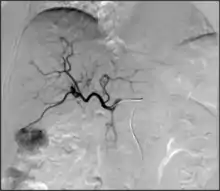

- Transarterial chemoembolization (TACE): Injection of a chemotherapy agent often with microparticles through a catheter into arteries feeding a tumor that both delivers chemotherapy and blocks the blood supply to the tumor to cause cell death[64]

TACE - Can be performed in different ways:

- Conventional transarterial chemoembolization (cTACE): Injection of lipiodol with high dose chemotherapy with or without microparticles directly into the tumor-feeding arteries.[65]

- Drug eluting bead transarterial chemoembolization (DEB-TACE): delivery of microparticles that are themselves loaded with the chemotherapy agent—typically doxorubicin or irinotecan.